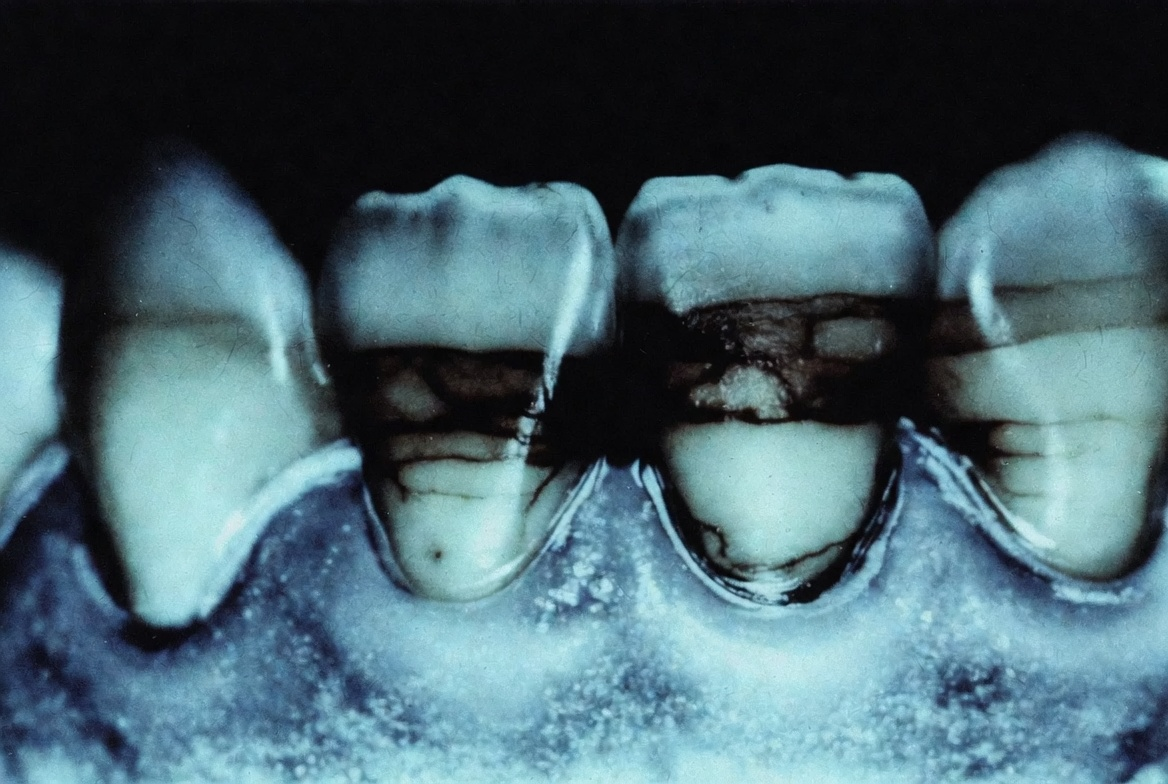

Лимон — самый разрушительный из трёх. Лимонная кислота расщепляет эмалевые призмы — структурные единицы эмали. pH лимонного сока около 2, эмаль начинает разрушаться при pH 5,5. Кислота вымывает минералы, эмаль становится пористой. Кариес развивается быстрее. Даже привычка пить воду с лимоном каждое утро незаметно разрушает защитный слой.

Сода — механическое абразивное действие. Царапает эмаль как наждачка, истончает её при регулярном применении, раздражает дёсны. Важный момент: сода убирает только внешний налёт. Никакого «отбеливания» в клиническом смысле не происходит — природный оттенок эмали не меняется.

Активированный уголь — максимальный риск при минимальном эффекте. British Dental Journal: исследователи не нашли доказательств эффективности зубных паст с углём. Consumer Reports: «угольные пасты могут принести больше вреда, чем пользы». На практике: истончение эмали, тёмные частицы застревают в трещинах и около пломб. И самое неожиданное — зубы после угля кажутся белее только потому что эмаль стёрта и обнажился более жёлтый дентин под ней.

На следующий день после офисного отбеливания — эмалевая резистентность соответствует «очень низкой» кариесрезистентности. Через 5–8 дней — умеренная. Через 14–30 дней с реминерализирующей терапией — показатели возвращаются к норме.

Вывод: профессиональное отбеливание временно снижает устойчивость эмали. При правильном протоколе — реминерализация сразу после процедуры — последствия обратимы.